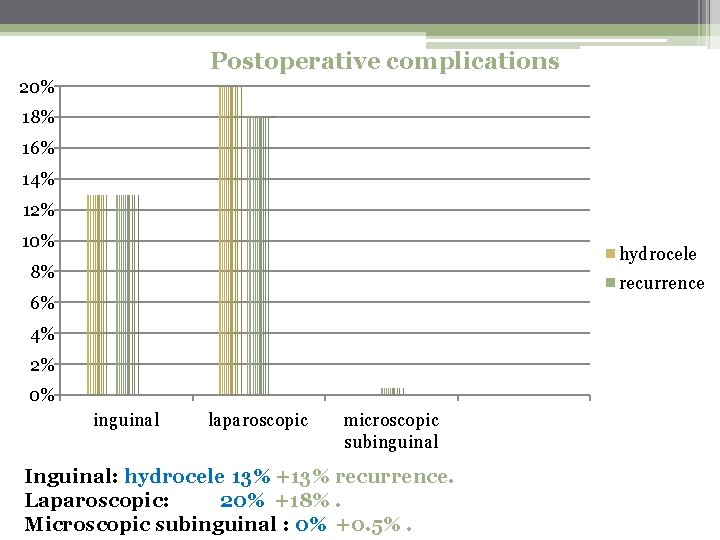

Objective: to compare the outcomes of the different surgical Techniques used in varicocelectomy wich include: Inguinal approach (40 p ) Laparoscopic approach (40 p) Subinguinal microscopic approach (40 p) The assessment included postoperative complications , and Postoperative semen analysis and pregnancy rate after 18 mon. The result was…………. .

Postoperative complications 20% 18% 16% 14% 12% 10% hydrocele 8% recurrence 6% 4% 2% 0% inguinal laparoscopic microscopic subinguinal Inguinal: hydrocele 13% +13% recurrence. Laparoscopic: 20% +18%. Microscopic subinguinal : 0% +0. 5%.

Conclusions The findings of our study have demonstrated That , compared with open inguinal , laparoscopic, and microscopic Sub inguinal microsurgical varicocelectomy offers The best outcomes.